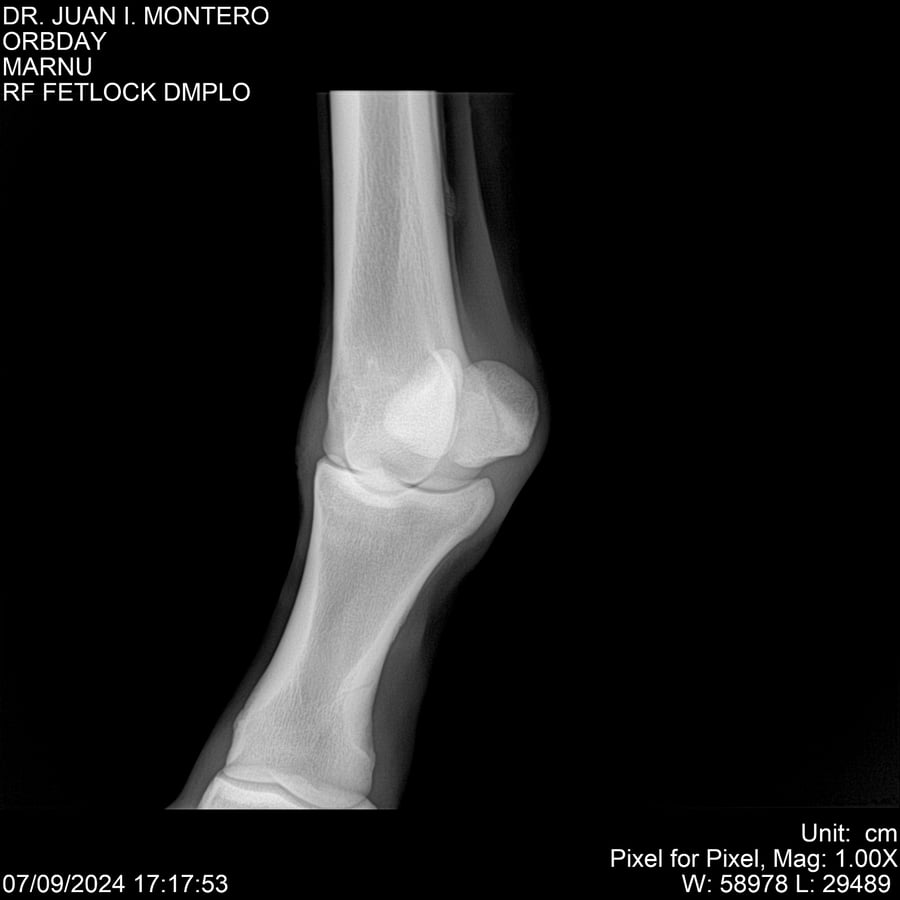

• Empresa: Abelenda N. R., Walter Hugo